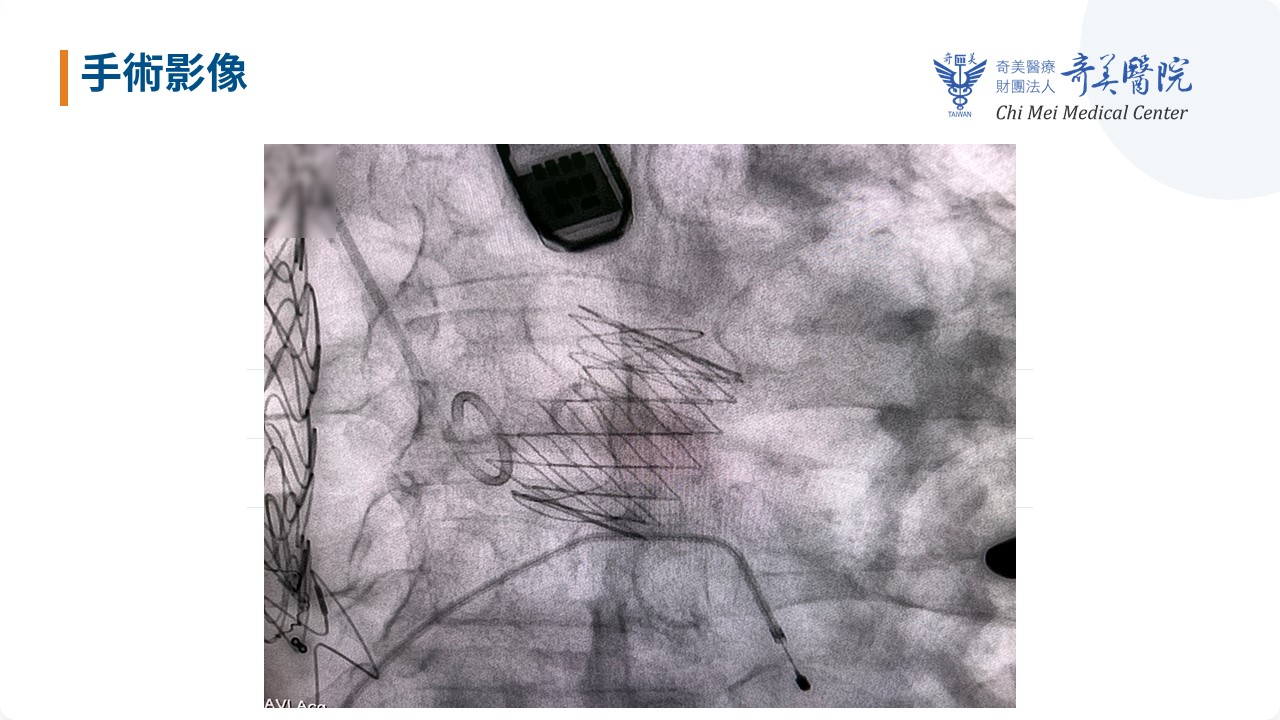

由於柯先生先前的繞道手術人工血管橫跨胸腔前方,若採傳統正中開胸手術,恐造成大出血與結構損傷,加上對傳統開胸手術意願低,經奇美醫療財團法人奇美醫院跨團隊完整評估後,採用經心尖(Transapical)的經導管主動脈瓣膜置換術(TAVI),由左胸小切口以微創方式直達心尖,避開原本彎彎曲曲的主動脈,與既有支架的危險路線,成功植入新型瓣膜裝置。整個過程僅耗時一個多小時,無

奇美醫院心臟血管外科主任吳南鈞、主治醫師李政亞與心臟血管內科主任施志遠、主治醫師涂冠杰共同帶領團隊,114年12月9日於南部率先成功完成「經心尖(Transapical)經導管主動脈瓣膜置換術(TAVI)」使用新型瓣膜裝置治療「純重度主動脈瓣逆流(AR)」的高難度個案。

由於病人嚴重瓣膜逆流導致心臟負荷加重,且合併多重複雜主動脈解剖與既往主動脈介入手術史,考量傳統正中開胸外科主動脈瓣置換(Surgical AVR)風險極高,團隊改採經心尖微創路徑成功完成瓣膜置換,術後恢復良好,8天即順利出院,充分展現奇美醫院在高難度結構性心臟病治療上與跨科整合照護的能力,即使是解剖複雜、風險極高的病人,也能獲得最安全、最適合的治療。